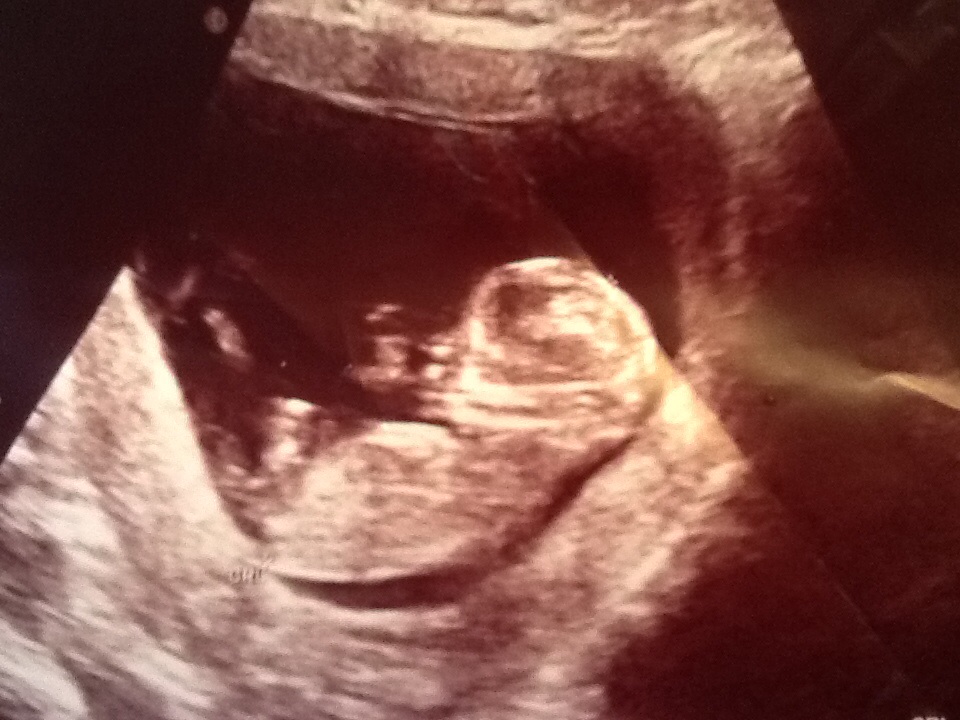

12 week scan- would welcome any gender guess, nub, skull or other!!

Attachment 25891I'd love if someone could take a look at my ultrasound pictures and make a gender guess. I've spent ages trying to work it out and am driving myself insane. My sonographer wasn't very kind when I asked could she make an early gender guess and made me feel very silly for asking!! I have a fabulous boy already, I'm pretending to everyone that I would be happy with either but would love a little girl. So far this pregnancy has been similar to my first so am thinking another boy on the way! Would be really grateful for any guesses...Attachment 25892 Attachment 25891Attachment 25893